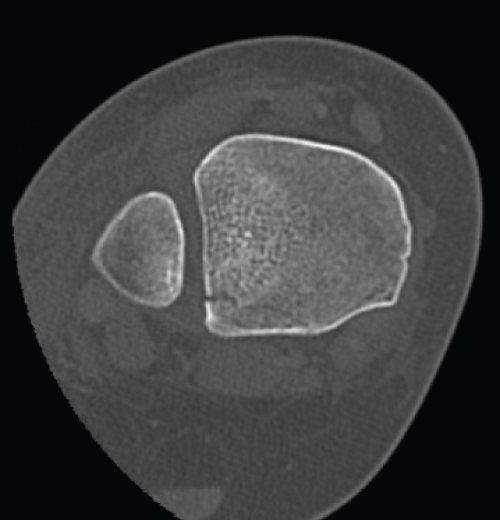

Posterior malleolus fractures are relatively common within the setting of ankle fractures, the most common of which are trimalleolar fracture with an incidence of approximately 7-14.2%. [5,6]. Isolated fractures of the posterolateral tibial lip (Volkmann's Triangle) are rare, with an estimated incidence of 0.5-1% [6,8,9]. The most common injury mechanism is SER, which accounts for the posterior inferior tibial fibular ligament avulsion fracture (Volkmann fracture) or posterior malleolus fractures, which may cause fibular rotational deformity or fibular shifting either anteriorly or posteriorly leading to syndesmotic instability (Figure 8A and Figure 8B). Injury mechanism of isolated Tillaux fracture is most likely PER, which is responsible for anterior inferior tibial fibular ligament avulsion fracture. The AITFL is intact but hinged on Tillaux fragment causing fibular rotation or shifting anteriorly leading to syndesmotic instability (Figure 3). The fibular rotational deformity or sagittal plane shifting is hardly to be assessed on plain radiographs. However, most of those injuries are missed from plain radiographs (Figure 8B).

Figure 8: Axial CT scans in patients with Volkmann fractures combined with other ankle fractures. (a) a 59-year-old female, internal fixation of medial and lateral malleoli fractures without fixation of Volkmann fracture was given. Pre- and postoperative plain radiographs did not reveal any syndesmotic instability but postoperative CT scans showed the fibula was shifted anteriorly due to Volkmann fragment which is hinged on PITFL and displaced laterally in posterior part of the syndesmosis causing syndesmotic incongruency and instability; (b) a 17-year-old male, plain radiographs did not reveal any syndesmotic instability; (c) CT scan showed that the Volkmann fragment was displaced posteriorly and medially causing fibular shifting posteriorly and malrotation that was a main cause syndesmotic incongruency.